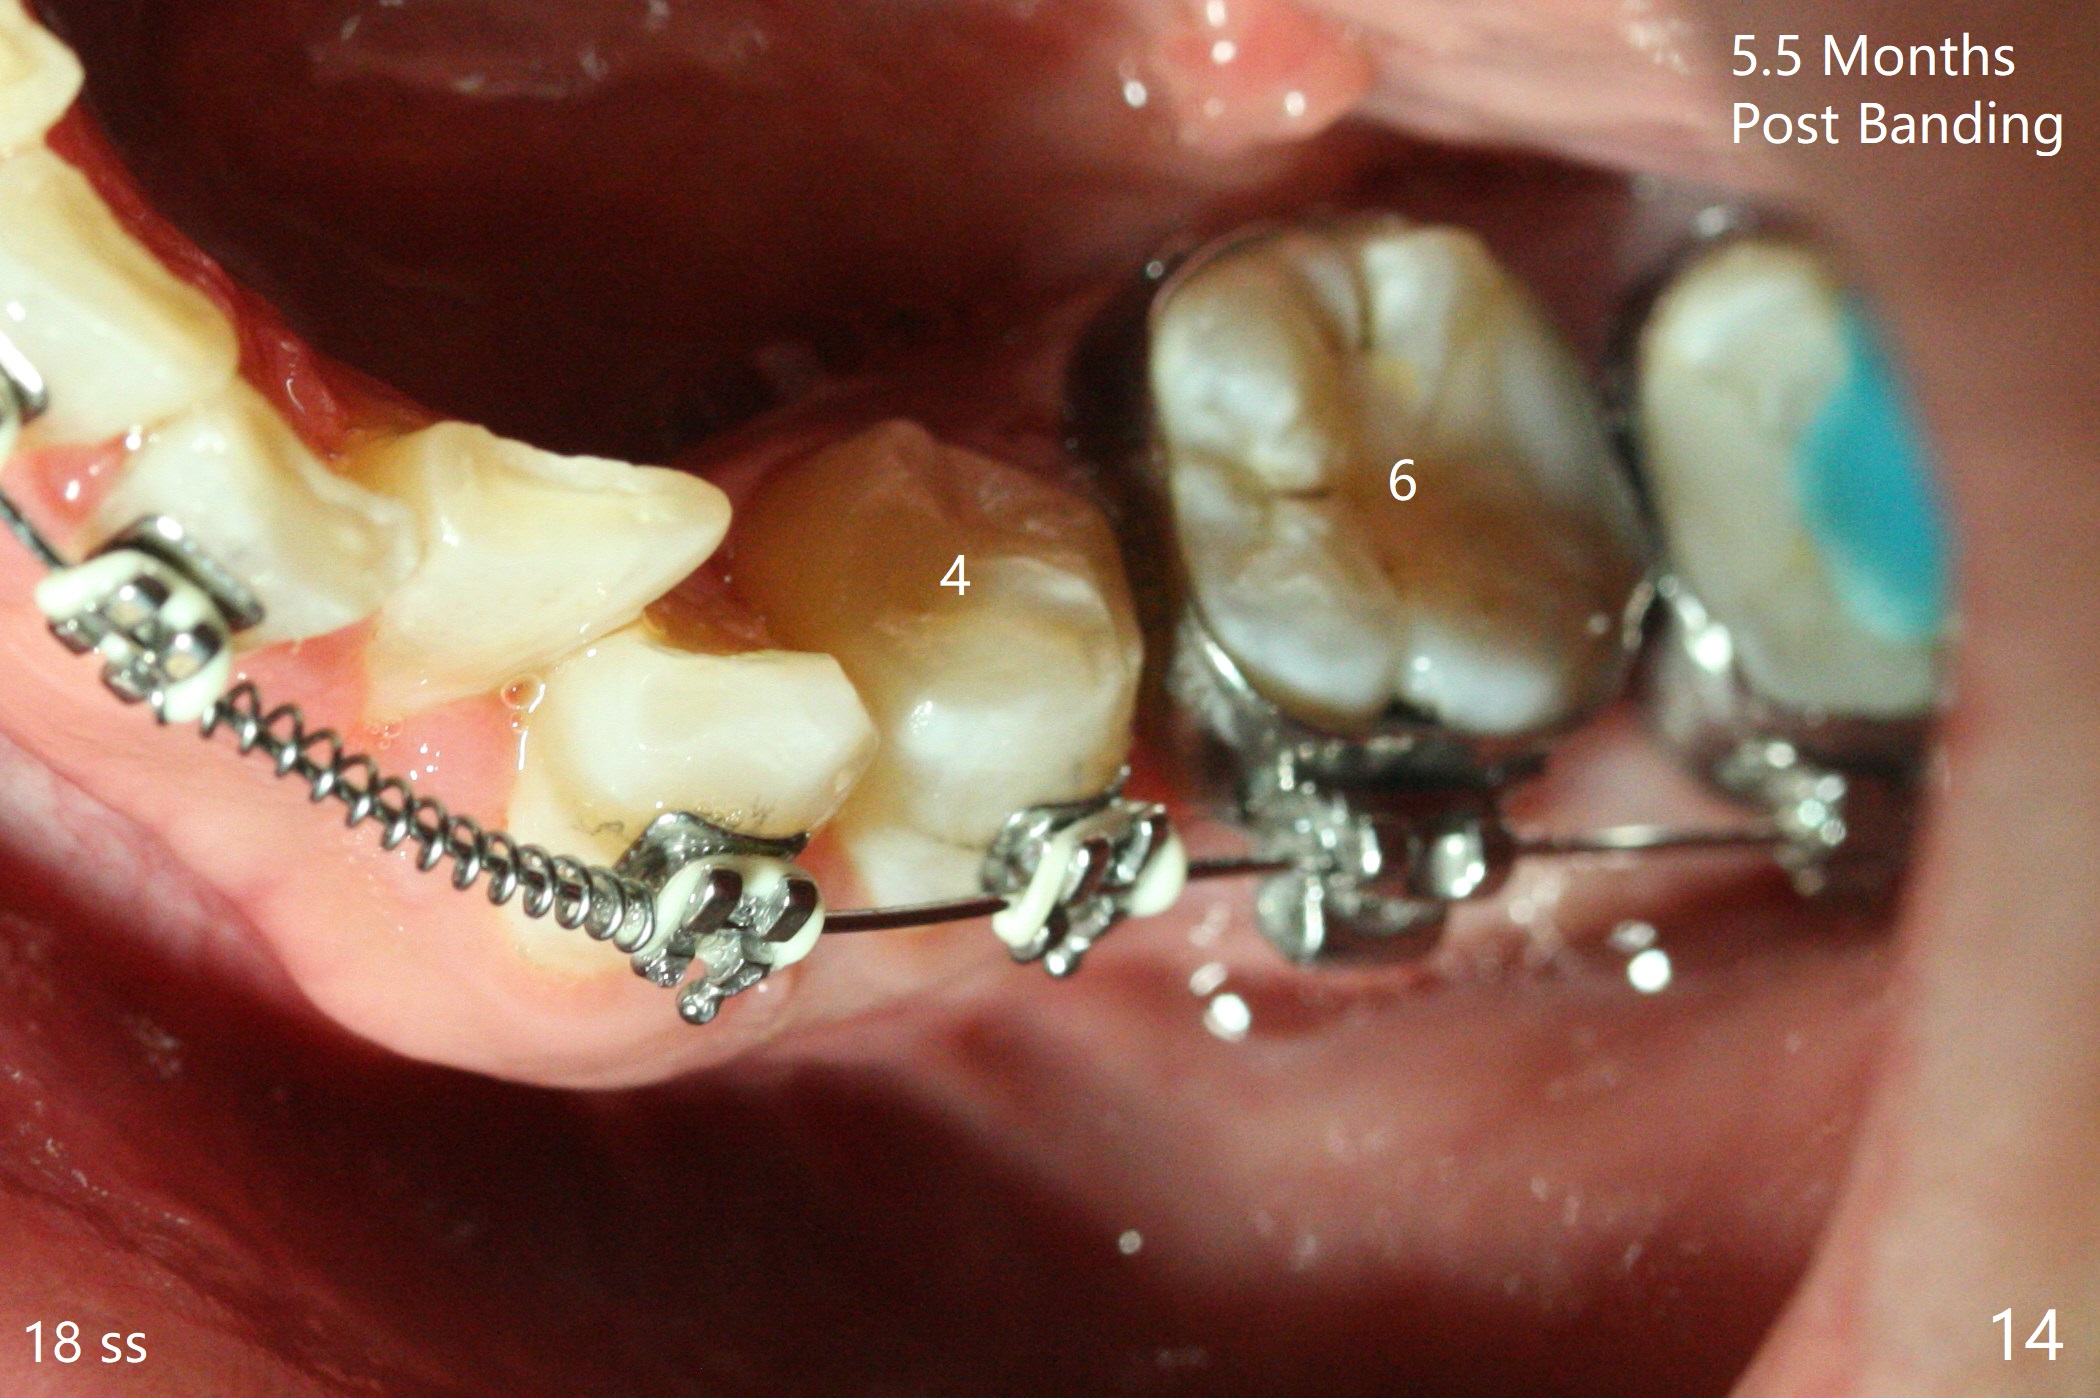

Severe crowding (Fig.1-7) appears to be alleviated especially 2 months after UR5 extraction. Diastemata seem to form mesial and distal to UR2 (Fig.8). Because of severe wear at UR3 (Fig.6), there is no bracket placement differential around it (Fig.8 (14 niti wire)). Lower bands and brackets are placed a week later (Fig.9-11). Because of tight space between LR4 and the opposing tooth (Fig.10), band adhesive is applied to L7 occlusal surface to open the bite (Fig.9). There is an abrupt kink of 12 niti wire between LL4 and 6 (Fig.11). The latter does not improve much in a month; the wires remain the same (Fig.12). For LL2, LR4 has been retracted for ~ 1 month (Fig.13). There is mild tension when 18 ss wire is inserted between LL4 and 6 five point five months post banding (Fig.14). UR4 has been distalized for a month using buccal power chains x3 resulting in rotation; to counter the rotation, a lingual button is placed with power chain x3 lingual and x2 buccal (Fig.15). With space gaining, it is time to finish definitive filling (Fig.16 *). Next visit check midlines, overjet, interdigitation, and molar classification. R4s distalize, but associate with rotation because of power chains buccal and lingual 8 months post banding (Fig.17,18). With the use of the same wires, power chains are applied lingual to continue distalization and rotation correction (Fig.20,21). Lingual buttons are placed at L2s buccalization (Fig.19) and mesialization (Fig.22,23). It appears that space should be created distal to LR3. That is that the lower anterior teeth should be shifted to the right, although it may be not appropriate for the midline.